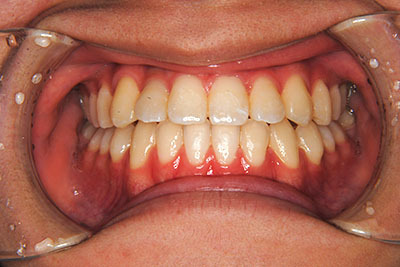

小学生高学年や中高生で矯正治療を考えている方へ

歯が乳歯から永久歯に生え変わった小学生高学年や、中高生でも矯正治療に手遅れということは全くありません。

成長中の顎の骨を矯正できたり、この時期の矯正はおとなになってから矯正治療を始めるよりも短期間で済むことがほとんどです。当院だとおおよそ1年で動的治療(マルチブラケット装置をつける期間)が終わることが多いです。